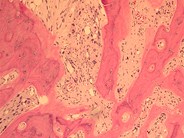

View Bone Marrow Fibrosis Myelofibrosis Pics. Bone marrow fibrosis is a critical component of primary myelofibrosis (pmf). Primary myelofibrosis (pmf) is a rare bone marrow blood cancer.

Myelofibrosis tends to come on slowly, and many people don't notice symptoms at first. Paget disease, secondary hyperparathyroidism in patients with vitamin d deficiency, renal. It is characterized by abnormal production of red blood cells, white blood cells, and platelets, in association with marrow fibrosis (scarring) and extramedullary hematopoiesis.1mesa.

One of the chronic myeloproliferative disorders, where there is replacement of bone marrow with collagenous connective tissue and progressive fibrosis secondary myelofibrosis. Paget disease, secondary hyperparathyroidism in patients with vitamin d deficiency, renal. Bone marrow fibrosis (bmf) plays an important role in the pathophysiology and the clinical outcomes of patients with primary myelofibrosis. Primary myelofibrosis (also called chronic idiopathic myelofibrosis, agnogenic myeloid metaplasia) is a disorder in which normal bone marrow tissue is gradually replaced primary myelofibrosis is only diagnosed when other causes of marrow fibrosis (including leukaemia, lymphoma, other types of.